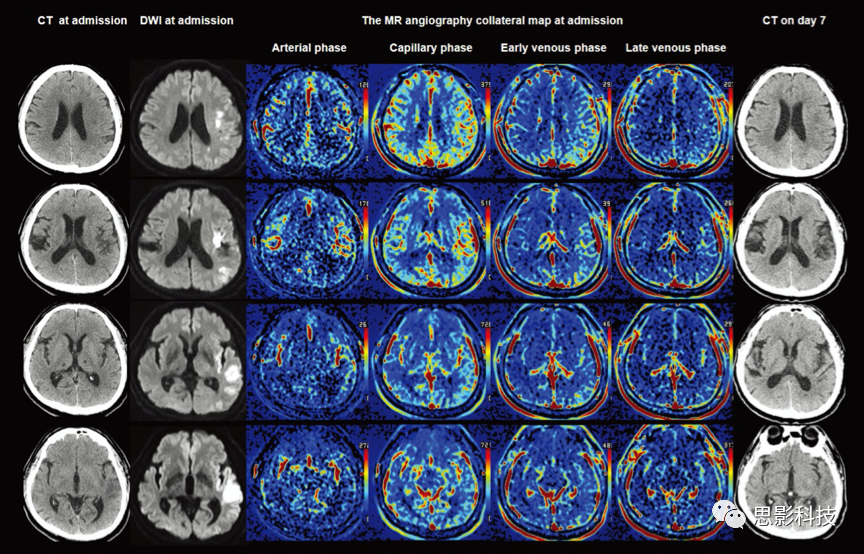

圖注:6級(jí)MR急性缺血性卒中側(cè)支(MAC)評(píng)分估算的MR血管造影側(cè)支圖分析的側(cè)支灌注分級(jí)系統(tǒng)。

MAC 5(優(yōu)秀):在美國(guó)國(guó)立衛(wèi)生研究院卒中量表(NIHSS)得分為6的64歲男性中,在癥狀發(fā)作后7小時(shí),進(jìn)行了MRI掃描的掃描。DCE-MR血管造影顯示嚴(yán)重的右大腦中動(dòng)脈(MCA)狹窄,而DWI顯示的是右MCA區(qū)域的皮質(zhì)和皮質(zhì)下區(qū)域的急性梗塞。在MR血管造影側(cè)支圖的代表性圖像上,在血管和神經(jīng)節(jié)水平,毛細(xì)管期沒(méi)有明顯的灌注延遲。其90天后改良的Rankin量表(mRS)得分為0。

MAC 4(良好):在一個(gè)80歲的NIHSS得分為10的男性中,在癥狀發(fā)作后6小時(shí)50分鐘進(jìn)行了MRI掃描。DCE-MR血管造影顯示右側(cè)近端頸內(nèi)動(dòng)脈狹窄,DWI顯示的急性梗塞主要發(fā)生在右腦邊界區(qū)域。在MR血管造影側(cè)支圖上,在毛細(xì)血管期,側(cè)支灌注延遲涉及不到MCA區(qū)域的一半,而在早期靜脈期無(wú)側(cè)支灌注延遲。90天后的mRS得分為1。

MAC 3(中級(jí)至良好):64歲的NIHSS評(píng)分為22的男性中,從癥狀發(fā)作后的1小時(shí)15分鐘進(jìn)行了MRI掃描。DCE-MR血管造影顯示右側(cè)的MCA閉塞,DWI顯示島狀和皮層下區(qū)域急性梗死。側(cè)支灌注延遲在毛細(xì)血管期涉及MCA區(qū)域的一半以上,在靜脈早期則保留一小部分。90天的mRS得分是2。

MAC 2(中級(jí)至較差):在一名85歲的NIHSS得分為21的女性中,在癥狀發(fā)作后5小時(shí)30分鐘進(jìn)行了MRI掃描。DCE-MR血管造影顯示右側(cè)MCA閉塞,DWI顯示額葉和頂葉急性梗死。側(cè)支灌注延遲涉及毛細(xì)血管期MCA區(qū)域的一半以上,早期靜脈期一半。90天的mRS得分為3。

MAC 1(較差):一名82歲的NIHSS評(píng)分為14的女性在癥狀發(fā)作后2小時(shí)進(jìn)行了MRI掃描。DCE-MR血管造影顯示右MCA閉塞,DWI顯示基底神經(jīng)節(jié)、腦島、額葉和后邊界區(qū)出現(xiàn)急性梗塞。并行灌注延遲在靜脈早期涉及MCA區(qū)域的一半以上,而在靜脈晚期則涉及不到一半。90天的mRS得分是5。

MAC 0(非常差):一名81歲的NIHSS評(píng)分為11的女性在癥狀發(fā)作1小時(shí)30分鐘后獲得MRI掃描。DCE-MR血管造影顯示右頸內(nèi)動(dòng)脈閉塞,MCA和DWI顯示嚴(yán)重急性梗塞。在超過(guò)一半的MCA區(qū)域中,側(cè)支灌注延遲一直持續(xù)到靜脈晚期。90天的mRS得分是5。